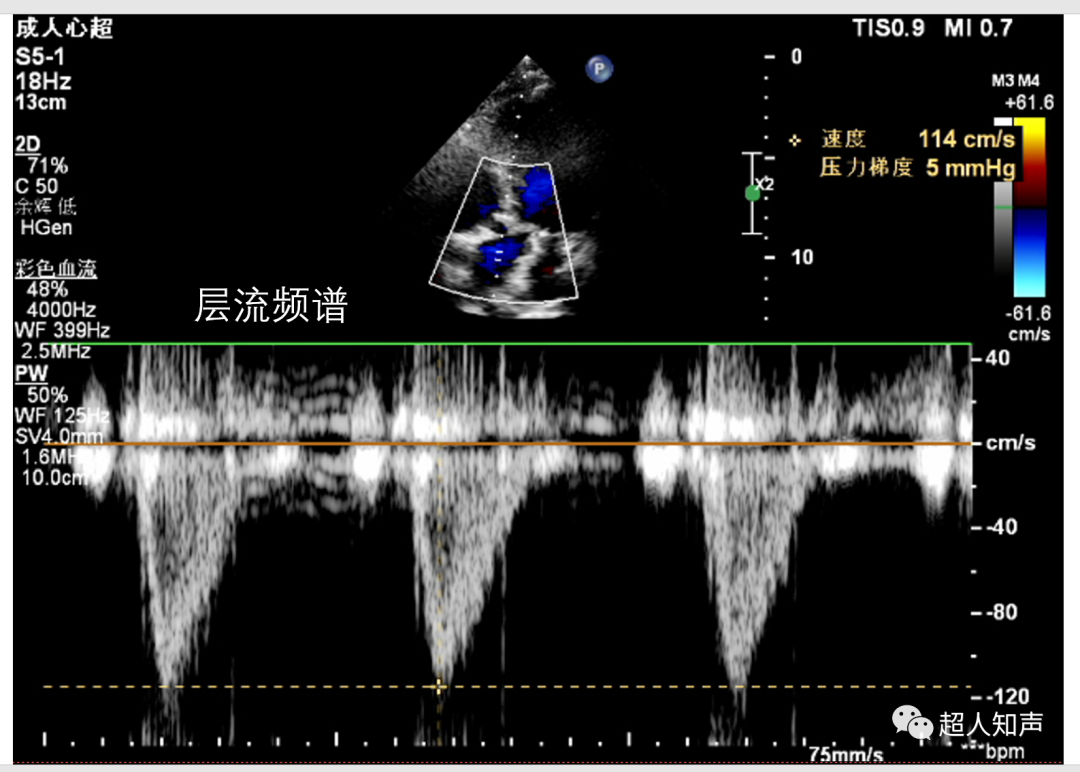

1、层流 为窄频谱,频谱波形规整、单向,频窗明显。频谱信号音柔和有乐感。